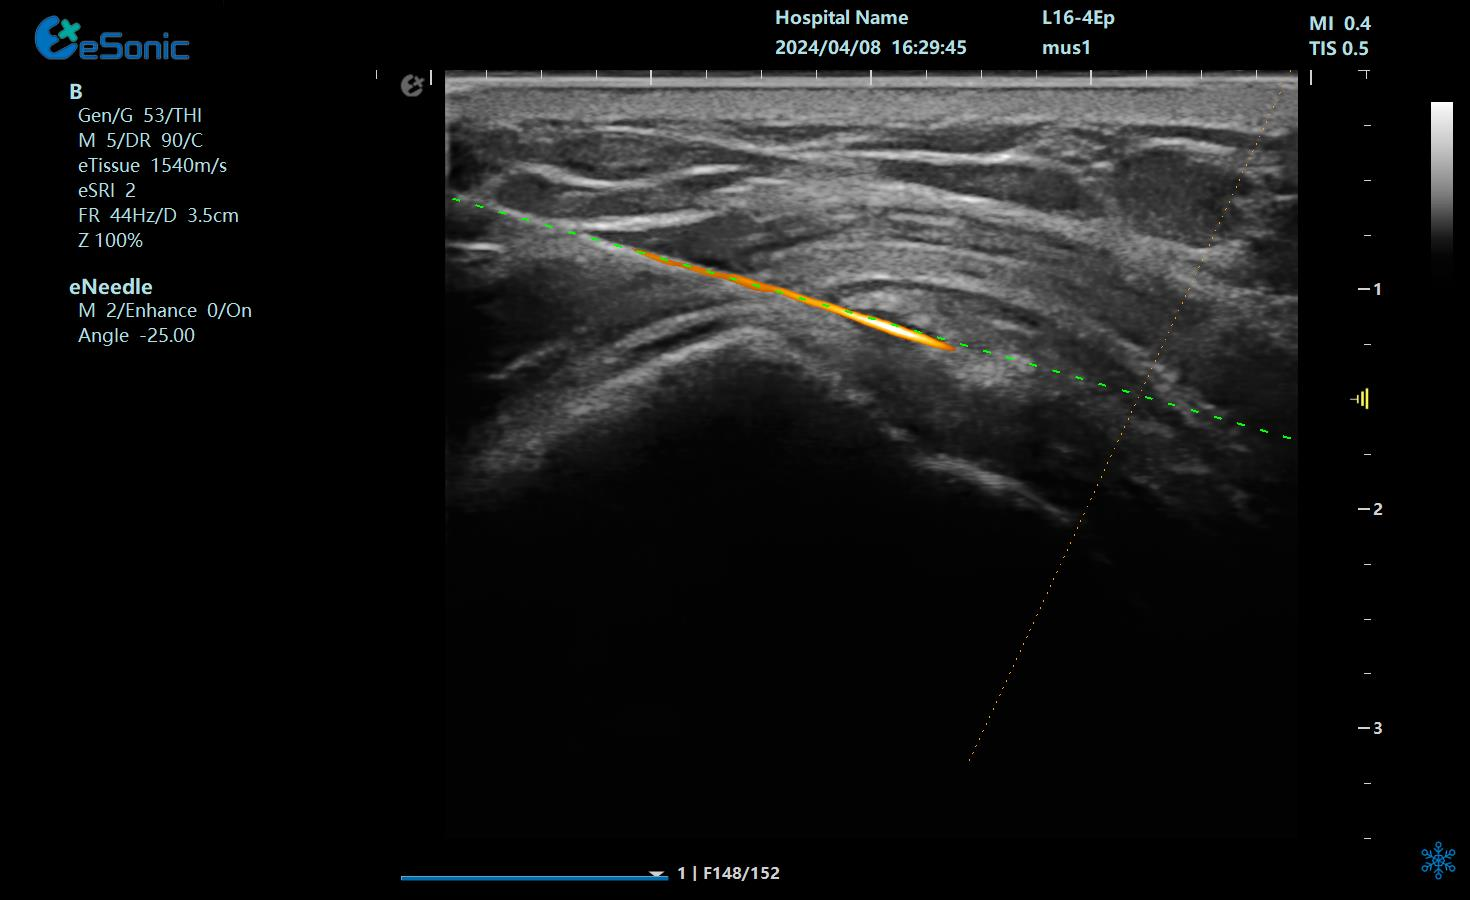

治疗中使用穿刺针智能Map和无磁导航技术

在超声图像中,穿刺针和钙化灶的显示都为强回声,常规的超声引导穿刺即使增强了穿刺针的显示仍不能有效地区分针尖和钙化灶,可能导致对穿刺部位的判断失误,往往比较依赖于医生的经验穿刺到钙化灶。

在与钙化性肌腱炎的斗争中,精准是胜利的关键。银河官网医疗的“Needle TsTM”技术凭借其智能Map技术和无磁导航系统,成功解决了传统超声引导穿刺中的难题,让针尖与钙化灶清晰可辨。这种创新不仅提高了手术的成功率,更减少了患者的痛苦和恢复时间。如今,我们不再需要担心手术中的不确定性和风险,因为“Needle TsTM”为我们提供了前所未有的精准保障。它让那些曾经困扰我们的“小石头”无处遁形,让康复之路变得更加顺畅。